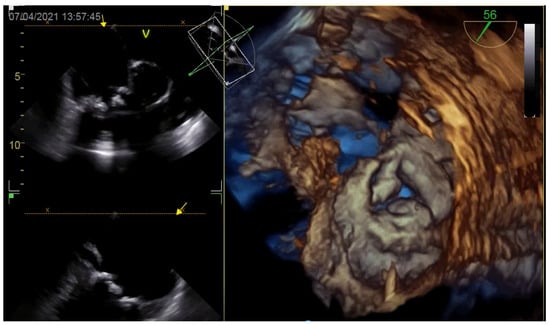

6.1. Procedure